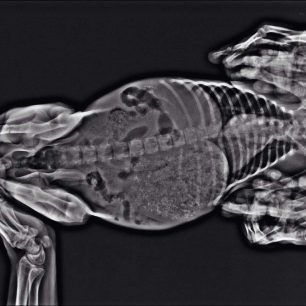

Το κουταβάκι που βλέπετε στις φωτογραφίες εντοπίστηκε χθες στο Άκτιο να κλαίει από τους πόνους κοντά στα διόδια της υποθαλάσσιας σήραγγας καθώς όπως αποδείχτηκε έχει σπασμένα τα δύο πόδια του ενώ είναι χτυπημένο και στην κοιλιά. Το πως τραυματίστηκε το ζώο παραμένει άγνωστο αν και σύμφωνα με τον κτηνίατρο Νίκο Ρώσσο, που το εξέτασε, κάποιος είναι πολύ πιθανό να το το κλώτσησε.

Η Δώρα Τσάτση μέλος του σωματείου «Παρέμβαση για τα Ζώα - Πρέβεζα» εξήγησε στο www.zoosos.gr ότι ο κ. Ρώσσος τους είπε πως είναι απίθανο το κουταβάκι, που ζυγίζει μόλις τέσσερα κιλά, να χτυπήθηκε από όχημα καθώς δεν έχει σημάδια και αυτά τα τραύματα προκαλούνται μόνο από κλωτσιά.

Εξαιτίας του νεαρού της ηλικίας του κουταβιού δεν θα γίνουν όλες οι επεμβάσεις ταυτόχρονα. Αρχικά θα χειρουργηθεί στην κοιλιά και στην συνέχεια θα ακολουθήσουν οι επεμβάσεις στο πίσω πόδι του που έχει σπάσει σε δύο σημεία και στη συνέχεια στο μπροστινό.